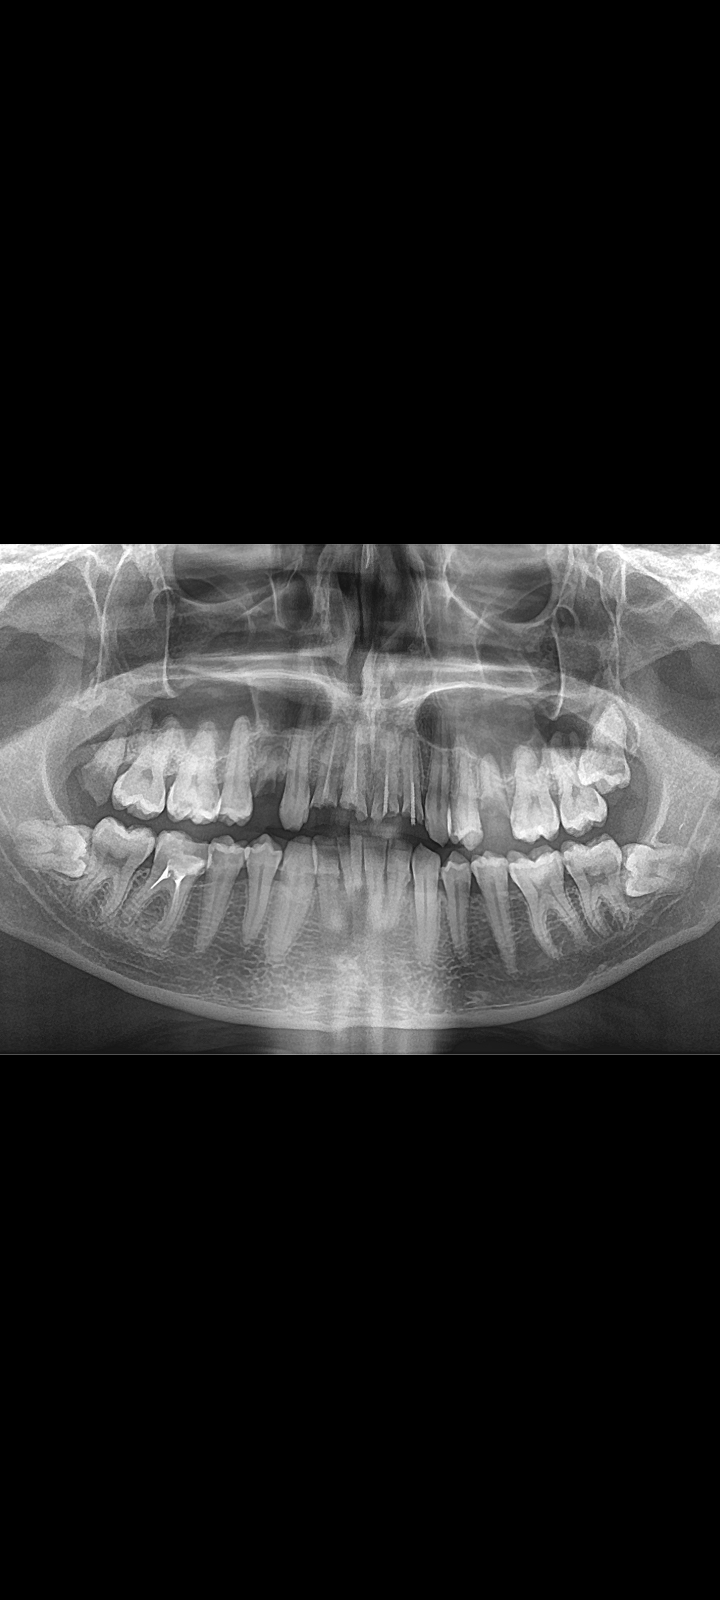

>Как профиль лица меняется после удаления восьмерок

Удаляли две, одну сверху другую снизу. Никаких изменений.

Но если у тебя они кривые и растут вбок например то конечно станет лучше

>>1633720